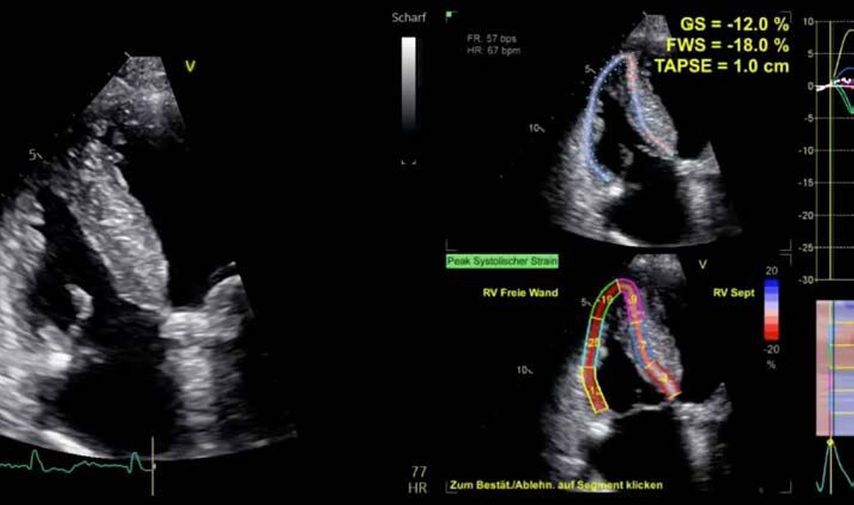

Im Echolabor des Pyhrn-Eisenwurzen Klinikums Steyr wird jede Form der Myokardwandverdickung mittels einer vollständigen Standardechokardiografie untersucht.2 Dabei wird auch ein Fokus auf die kontrastmittelunterstützte Sonografie gelegt, um die tatsächliche Dicke des Myokards zu vermessen.3 Die Verdickung sollte optimalerweise mittels 3D-LV-Massenmessung erfolgen. Die Messung im 2D-Bild ist dahingehend unterlegen. Ebenso wird jede Myokardwandverdickung mittels 2D-„strain imaging“ in der transthorakalen Echokardiografie (TTE) untersucht.4–6 Der „strain“ ist eine Messung der longitudinalen Funktion des Herzens (Video 1).

3., 4. & 5. Fall: andere Formen der Myokardwandverdickung, männlich, 44a & 32a, und weiblich, 72a

Andere Formen der Myokardwandverdickung, die mit „strain“ und MRT gut dargestellt werden können, sind einerseits die Differenzierung der Auswirkung der arteriellen Hypertonie (weiblich, 72a) bei Vorliegen einer Herzinsuffizienz mit normaler EF, einem GLS von –15,4%, einem LA-„strain“, in Reservoirphase 25% bei gering verlängerten T1-Zeiten im MRT. Andererseits kann Steroidabusus (männlich, 44a) zu einem reduzierten „strain“ mit gering verlängerten T1-Zeiten und einer Normalisierung der bildgebenden Befunde nach 2 Jahren nach Absetzen führen bzw. eine Mitochondriopathie (männlich, 32a) zu einer unklaren Myokardverdickung mit diffus reduziertem „strain“ und reduzierter LV-Funktion.4,11,12